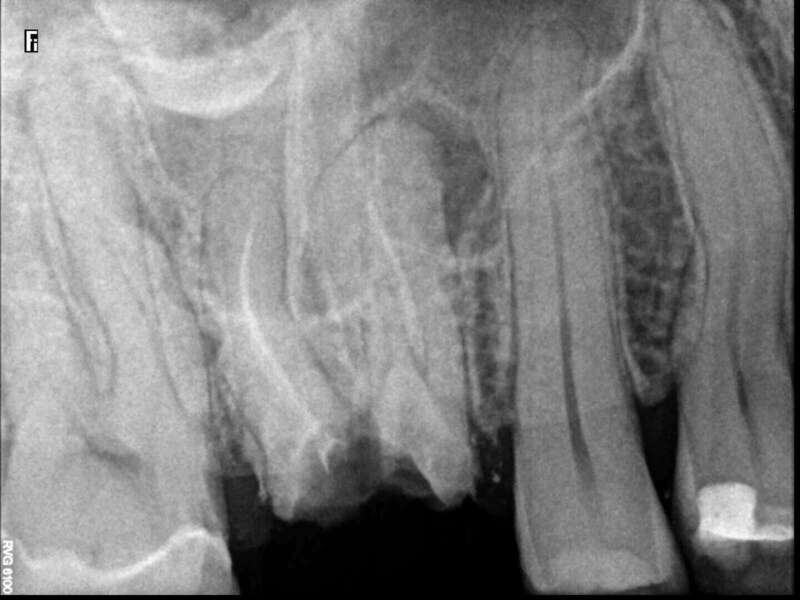

Avant

Après